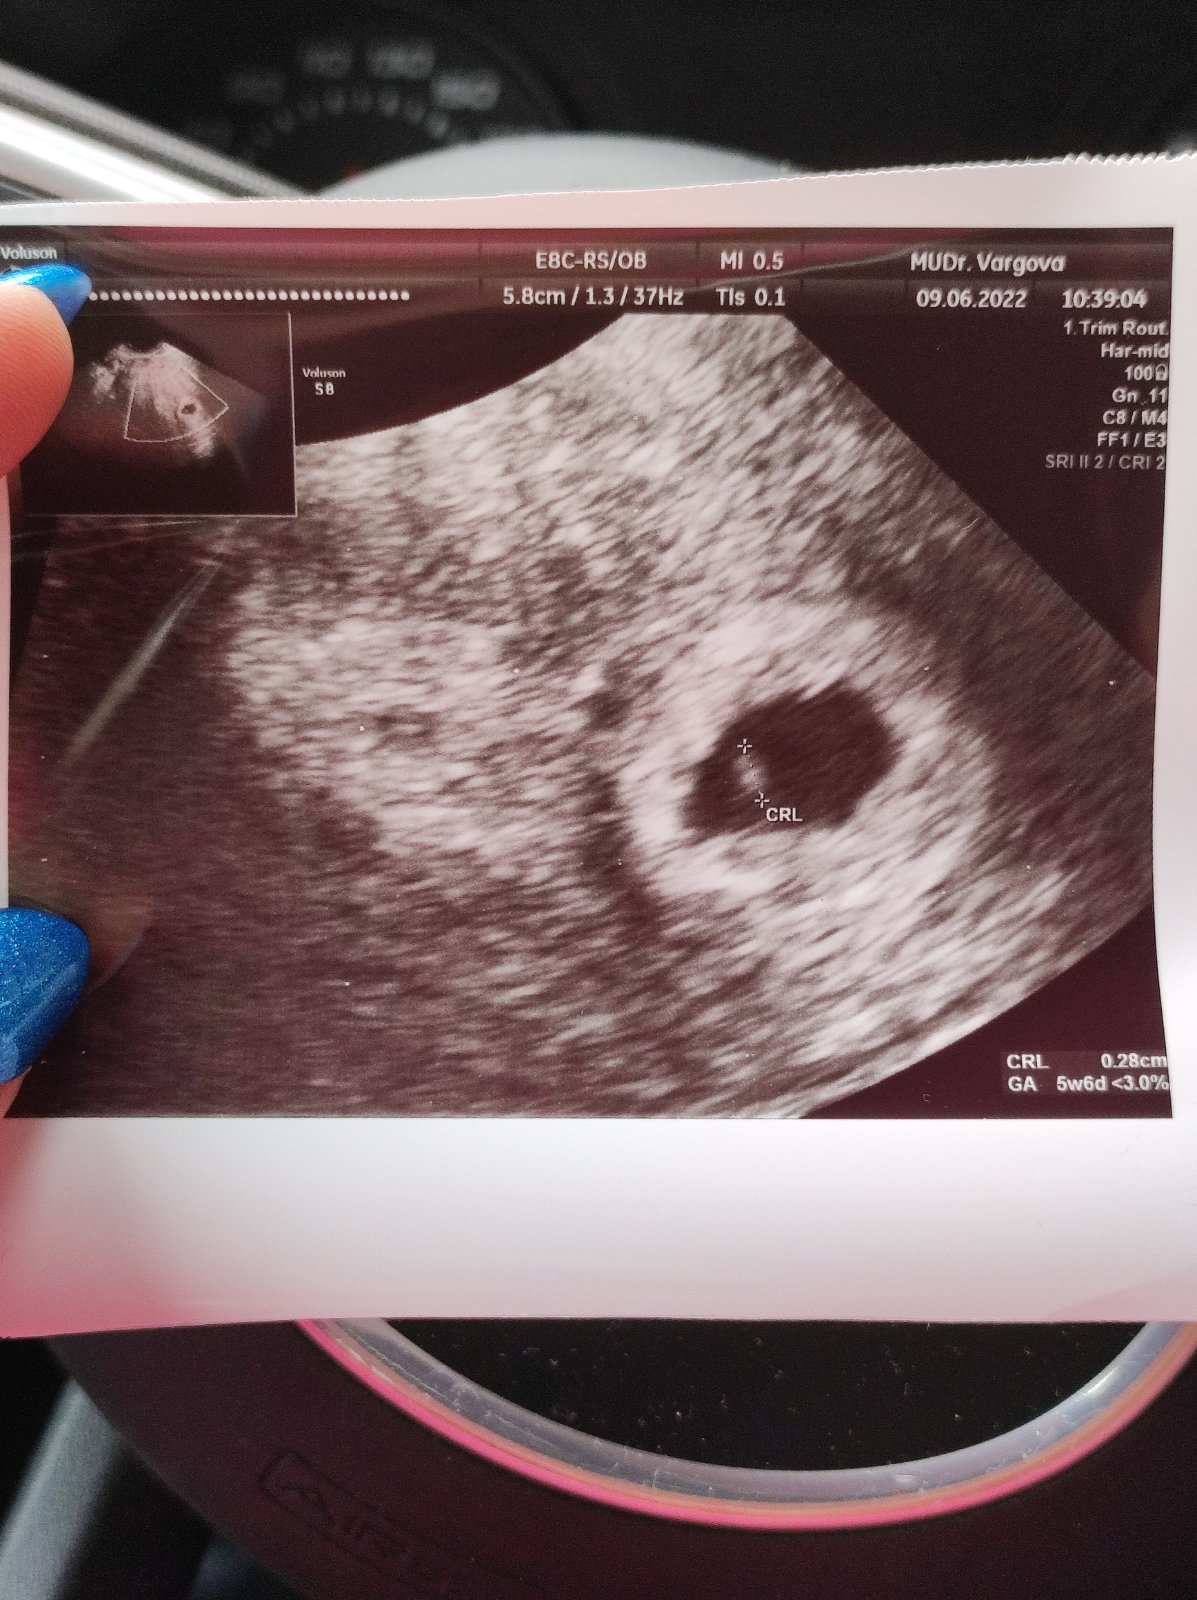

Tak zienky dnes som bola u doktorky,tehotenstvo potvrdila,som vraj 5+3,na sone videla vak aj nieco drobne vnutri🥰ale kedze som mala predtym dva krat MA,tak mi predpisala progestanelle na vkladanie a anopyrin a o tyzden na kontrolu…